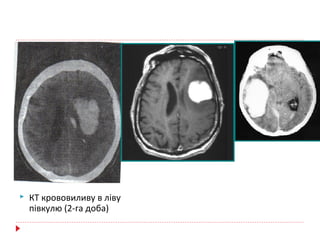

 КТ крововиливу в ліву

півкулю (2-га доба)